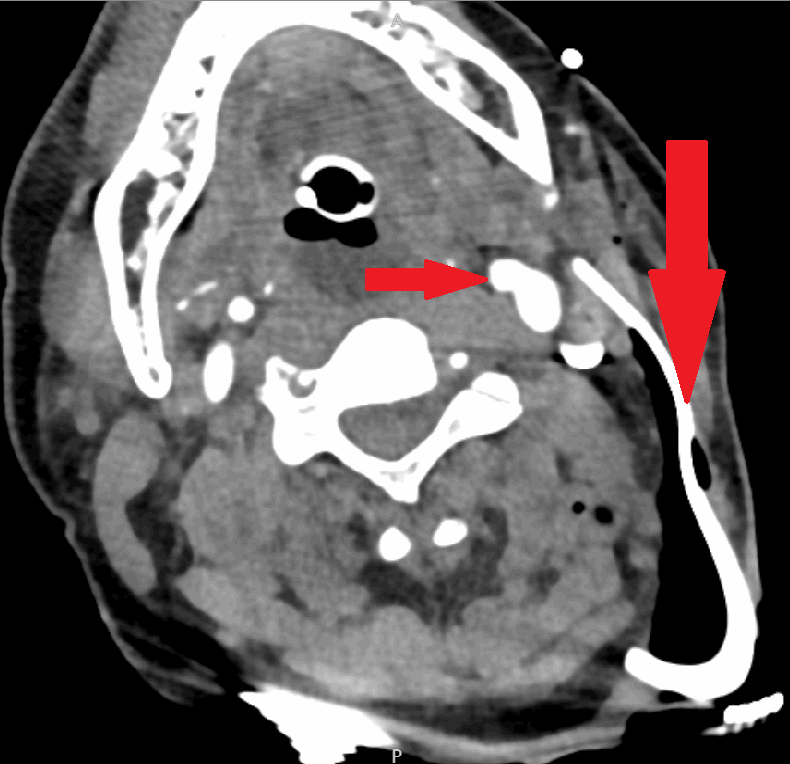

On arrival, the patient was talking and protecting his airway. He was tachycardic with a heart rate of 140 bpm. He was hypotensive with systolic blood pressure of 70 mmHg. His Glasgow Coma Scale was 9. The patient was resuscitated according to Advanced Trauma Life Support protocol with blood products as well as minimal crystalloid with the assumption that the patient had bled significantly on scene. The patient responded appropriately to minimal volume resuscitation evidenced by the stabilization of his vital signs. He was intoxicated, agitated and deemed to be a threat to himself and others, and was therefore intubated. Removal of the foreign body was thought to be best suited in the operating room in a well-controlled environment based on the abutment of the object to the surrounding vascular and nervous structures as well as to ensure the retrieval of all foreign material. It is also important to note the need for personal protection and safety of the surgical team members when dealing with sharp foreign bodies and therefore this controlled environment would be optimum. Given that he became hemodynamically stable with minimal volume resuscitation, he was taken for a CT angiogram (Figure 2 and Figure 3), which revealed the distal tip of a glass beer bottle closely approximating the posterolateral internal jugular vein without evident extravasation and no evidence of trauma to any other surrounding vasculature. The foreign body extended through the anteromedial aspect of the left sternocleidomastoid muscle and entered the left posterolateral paraspinal musculature.

Figure 2. CT angiography of the head and neck demonstrating foreign body abutting major vasculature.